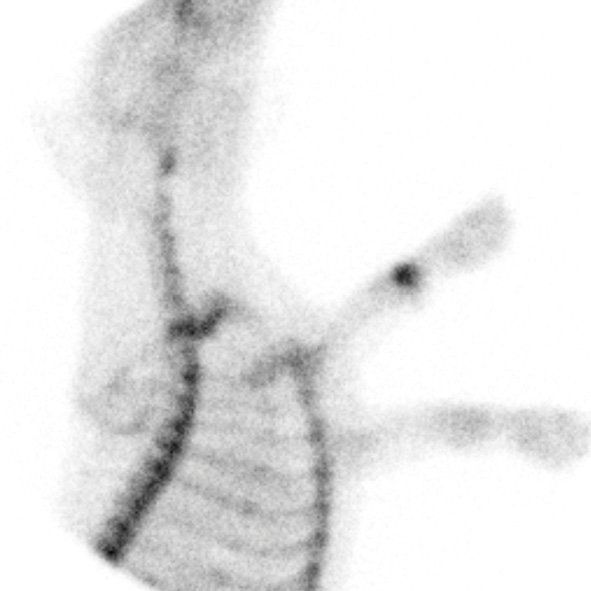

Bone Scintigraphy